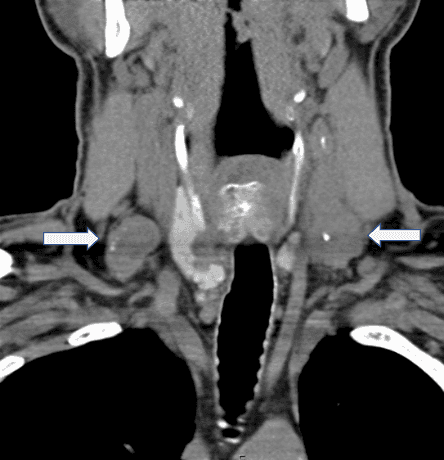

患者は61歳の男性で、両側の持続性転移性PTCが両側の頸部リンパ節区画に現れます。2014年には、兄弟姉妹が乳頭状甲状腺がんと診断されたため、甲状腺がんの検診を受けました。 2014年3月に外部施設で全甲状腺摘出術を受け、その際右甲状腺PTCが右回回喉頭神経に付着していることが確認されました。最終病理では両側性PTCが認められ、最大の腫瘍は左側に3.1cmで甲状腺外拡張がありました。6つのリンパ節のうち3つにPTCが含まれていました。術前には頸部のCTスキャンを受けており、両側側の外側頸部リンパ節腫異が転移性疾患と一致することが明確に示されました(図1)。しかし、外側首の病気は、原因不明のまま、最初の手術では一度も治療されませんでした。手術後も声に問題があり、術後も声の疲労に悩まされていました。2014年4月に放射性ヨウ素134mCiで治療されました。治療後のヨウ素スキャンでは転移性疾患の証拠は見られませんでしたが、サイログロブリン値が持続的に上昇していました。

首と胸部のCTスキャンを受けたところ、首の軟部組織に異常なリンパ節が見られ、一部には病理的な肥大、石灰化、中心性壊死が見られ、転移性疾患の疑いが示されました。代表例としては、隣接する内頸静脈を狭める3cmの左レベルIIIリンパ節、2.1cmの右レベル3リンパ節、頸動脈前方の9mm左レベルII/IIIリンパ節、そして右鎖骨下静脈と右内頸静脈の分岐部に接する可能性のあるリンパ節があります。 左レベルIV/鎖骨上リンパ節は1.7cmでした。